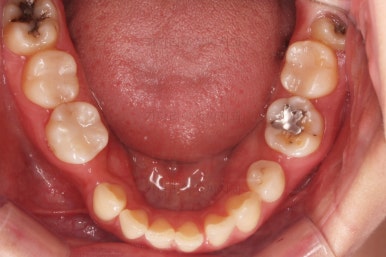

초진 시 입안의 모습인데요.

왜 그런지 비밀이 풀리는 것 같죠?

윗니는 한 쪽이 치아 2개가 결손이면서 유치가 하나 남아있고요.

아랫니는 한 쪽은 1개, 반대편은 2개 치아가 결손이었습니다.

도합 5개의 치아가 결손이었는데요.

결손 위치의 갯수가 위아래 좌우 다 달라서 중앙선이 맞을래야 맞을 수가 없는 상황이었죠.

결손치아 주위 치아들은 쓰러지고 비틀어져 있어서 장기적으로 좋지 못한 상황이었고요.

좀 더 디테일하게 윗니 작은 앞니 1개가 왜소치아라서 치아 크기도 맞지 않은 상황이었습니다.

유치 발치 공간은 1개 사이즈로만 남기고 줄여 나가기로 했어요.

아랫니도 1개 빈공간은 없애고, 2개 빈공간은 1개 사이즈로만 남기기로 했습니다.